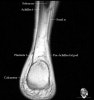

- Coronal section

The coronal oblique T1 sequence follows the tendons of the ankle around the malleolar turns and also evaluates the medial ankle ligaments.

The coronal oblique PD fat suppressed sequence follows the tendons of the ankle around the malleolar turns and is particularly important in evaluation of the Posterior tibialis tendon.

Bone and marrow

Talar dome

Deltoid ligament

Tendons in arch

Plantar fascia

Troubleshoot ligaments